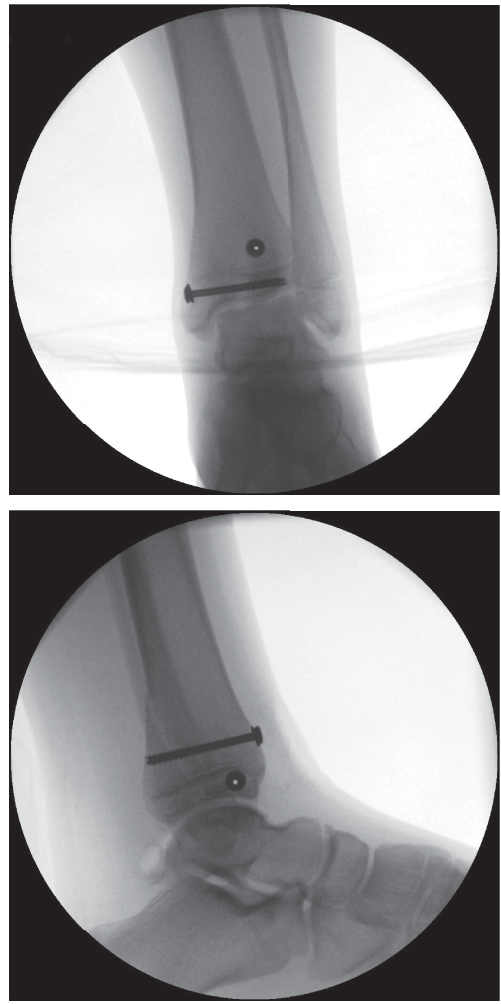

* Caption: Post-operative radiograph demonstrating appropriate fixation of a Tillaux fracture with two cannulated screws. Note the trajectory of the screws, aiming for stable interfragmentary compression while minimizing physeal disturbance.